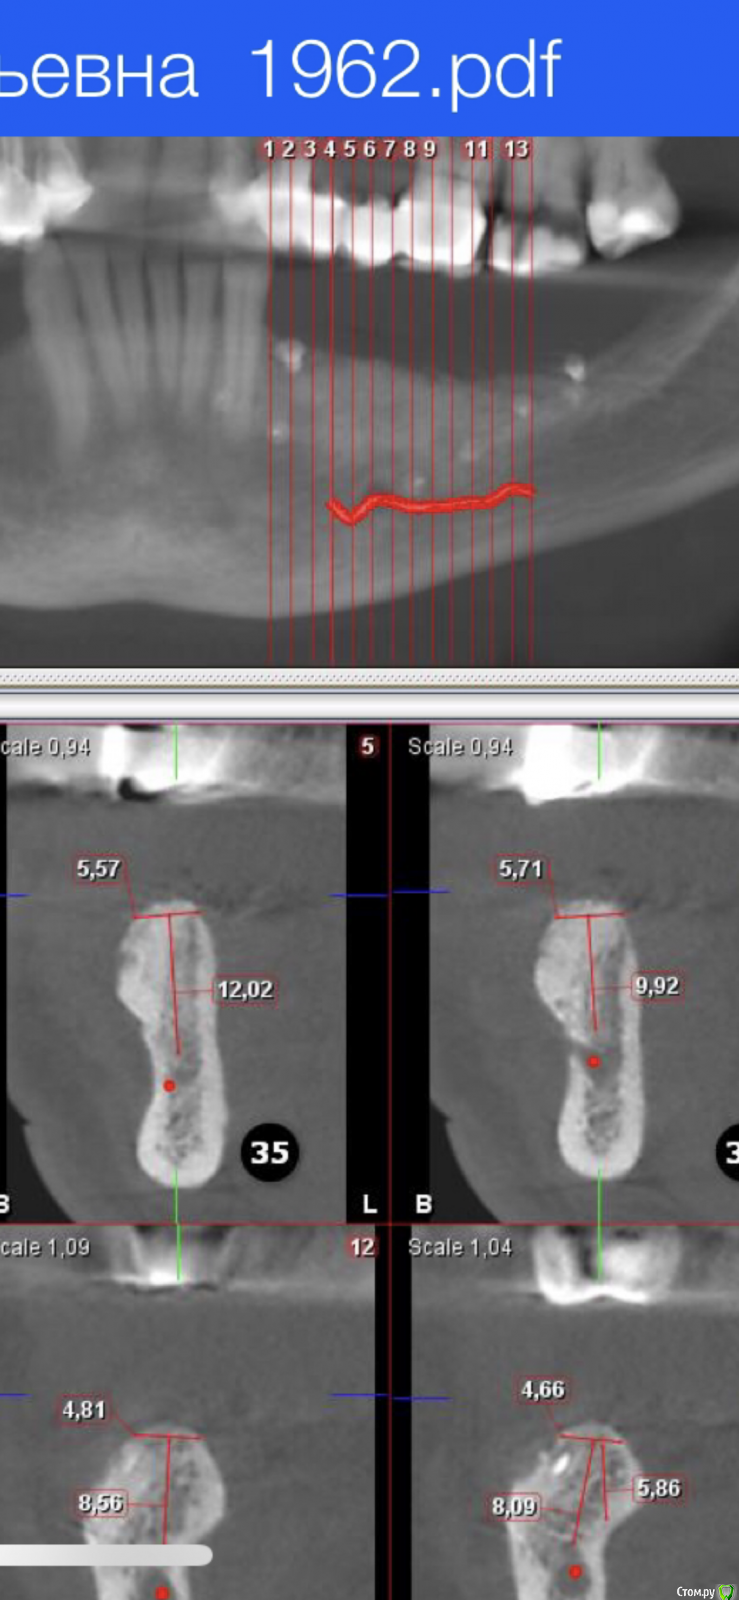

Nazim_NV86 Опубликовано 30 июня, 2020 Поделиться Опубликовано 30 июня, 2020 (изменено) Что сделать с правым низом ? Подкину вам пищу для размышлений.45 оголён прилично. -+3мм. Урбанизировать не возьмусь. До просмотра КЛКТ была мысль удалить его и "ламинировать" область 44,45 по пикам. Теперь что-то жалко стало. "база" не широкая. Изменено 30 июня, 2020 пользователем Nazim_NV86 Ссылка на комментарий

Александр07 Опубликовано 1 июля, 2020 Поделиться Опубликовано 1 июля, 2020 Я бы 4.5 убрал, нкр по ширине и через 6 мес 2 импл Ссылка на комментарий

Nazim_NV86 Опубликовано 4 июля, 2020 Автор Поделиться Опубликовано 4 июля, 2020 Я бы 4.5 убрал, нкр по ширине и через 6 мес 2 имплменя смущает толщина базальной части и острый ножевидный гребень. Боюсь сосидж не даст нормальной ширины, а высоту даже можно потерять 1-1.5мм. Каркасными птфе не пользуюсь, мне там проще ламину(-ы) прибить. Ссылка на комментарий

Александр07 Опубликовано 8 июля, 2020 Поделиться Опубликовано 8 июля, 2020 меня смущает толщина базальной части и острый ножевидный гребень. Боюсь сосидж не даст нормальной ширины, а высоту даже можно потерять 1-1.5мм. Каркасными птфе не пользуюсь, мне там проще ламину(-ы) прибить. Ортодонтия интересный вариант, если не не рассматривать то сосидж с биогайдом наверно самый безопасный вариант, высота хорошая если даже потеряете немного то не страшно , думаю надо побольше ауто и перфорировать кортикалку хорошо , Вот похожий случай , но по срезам в основании пошире 1 Ссылка на комментарий